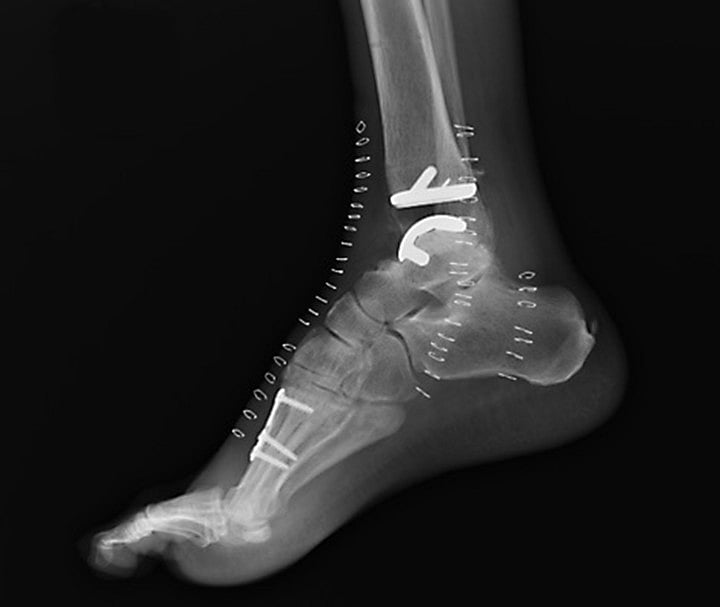

But now some orthopaedic surgeons are performing total ankle replacements, in which bone and tissue are removed to make way for highly sophisticated metal and plastic implants. These doctors say that the procedure, which has taken decades to improve, is highly effective at relieving arthritic pain and enabling patients to regain the use of their ankle and resume a more active life.

This turnabout in medical treatment is due largely to the development of a half-dozen implant devices that were approved by the Food and Drug Administration beginning in the early 1990s. These prosthetic devices — made of advanced metal alloy and plastic — cover both the major shin bone and the ankle bone and are engineered to interact with each other and the patient’s body in a way that maximises mobility and flexibility.

Parekh cut into the front of the ankle and down through the soft tissue all the way to the bone. Then he cut away from both sides of the joint to make way for the implant. He removed enough bone to install two metal pieces and a plastic piece — called the Cadence total ankle replacement — to hold the ankle together and provide it with flexibility. Then he stitched up the repaired joint.